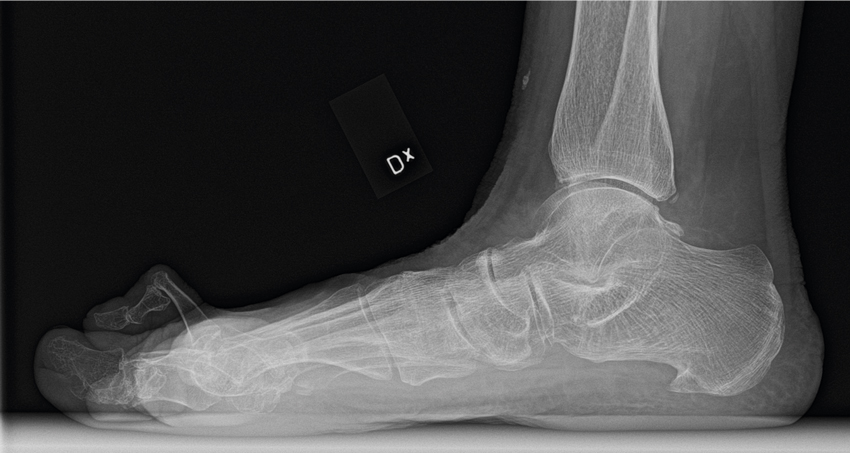

Slätröntgen i sidoprojektion med belastning. Notera hammartå i andra tån.

• Slätröntgen med belastning bör genomföras vid misstänkt hallux rigidus i standardprojektioner (frontal- och sidobild).